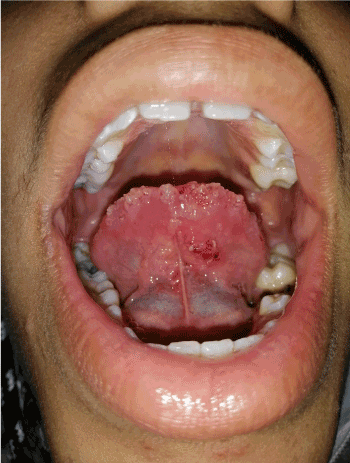

Young patient of 13 years, in good health, consults for asymptomatic lesions of the tongue evolving since birth.

On examination, we noted, on the dorsal surface of the tongue, a hypertrophic plaque, made of multiple yellowish and translucent vesicles, they are hematic in places, the lesion overflowed on the free edge, without reaching the floor of the tongue. No deep mass was found.

Figure 1. On the tip and ventral surface of the tongue, there are some vesicles of the same characteristics, without lesions on the floor

Figure 2. Clinical photos of the tongue showing multiple vesicles with translucent and yellowish contents, sometimes